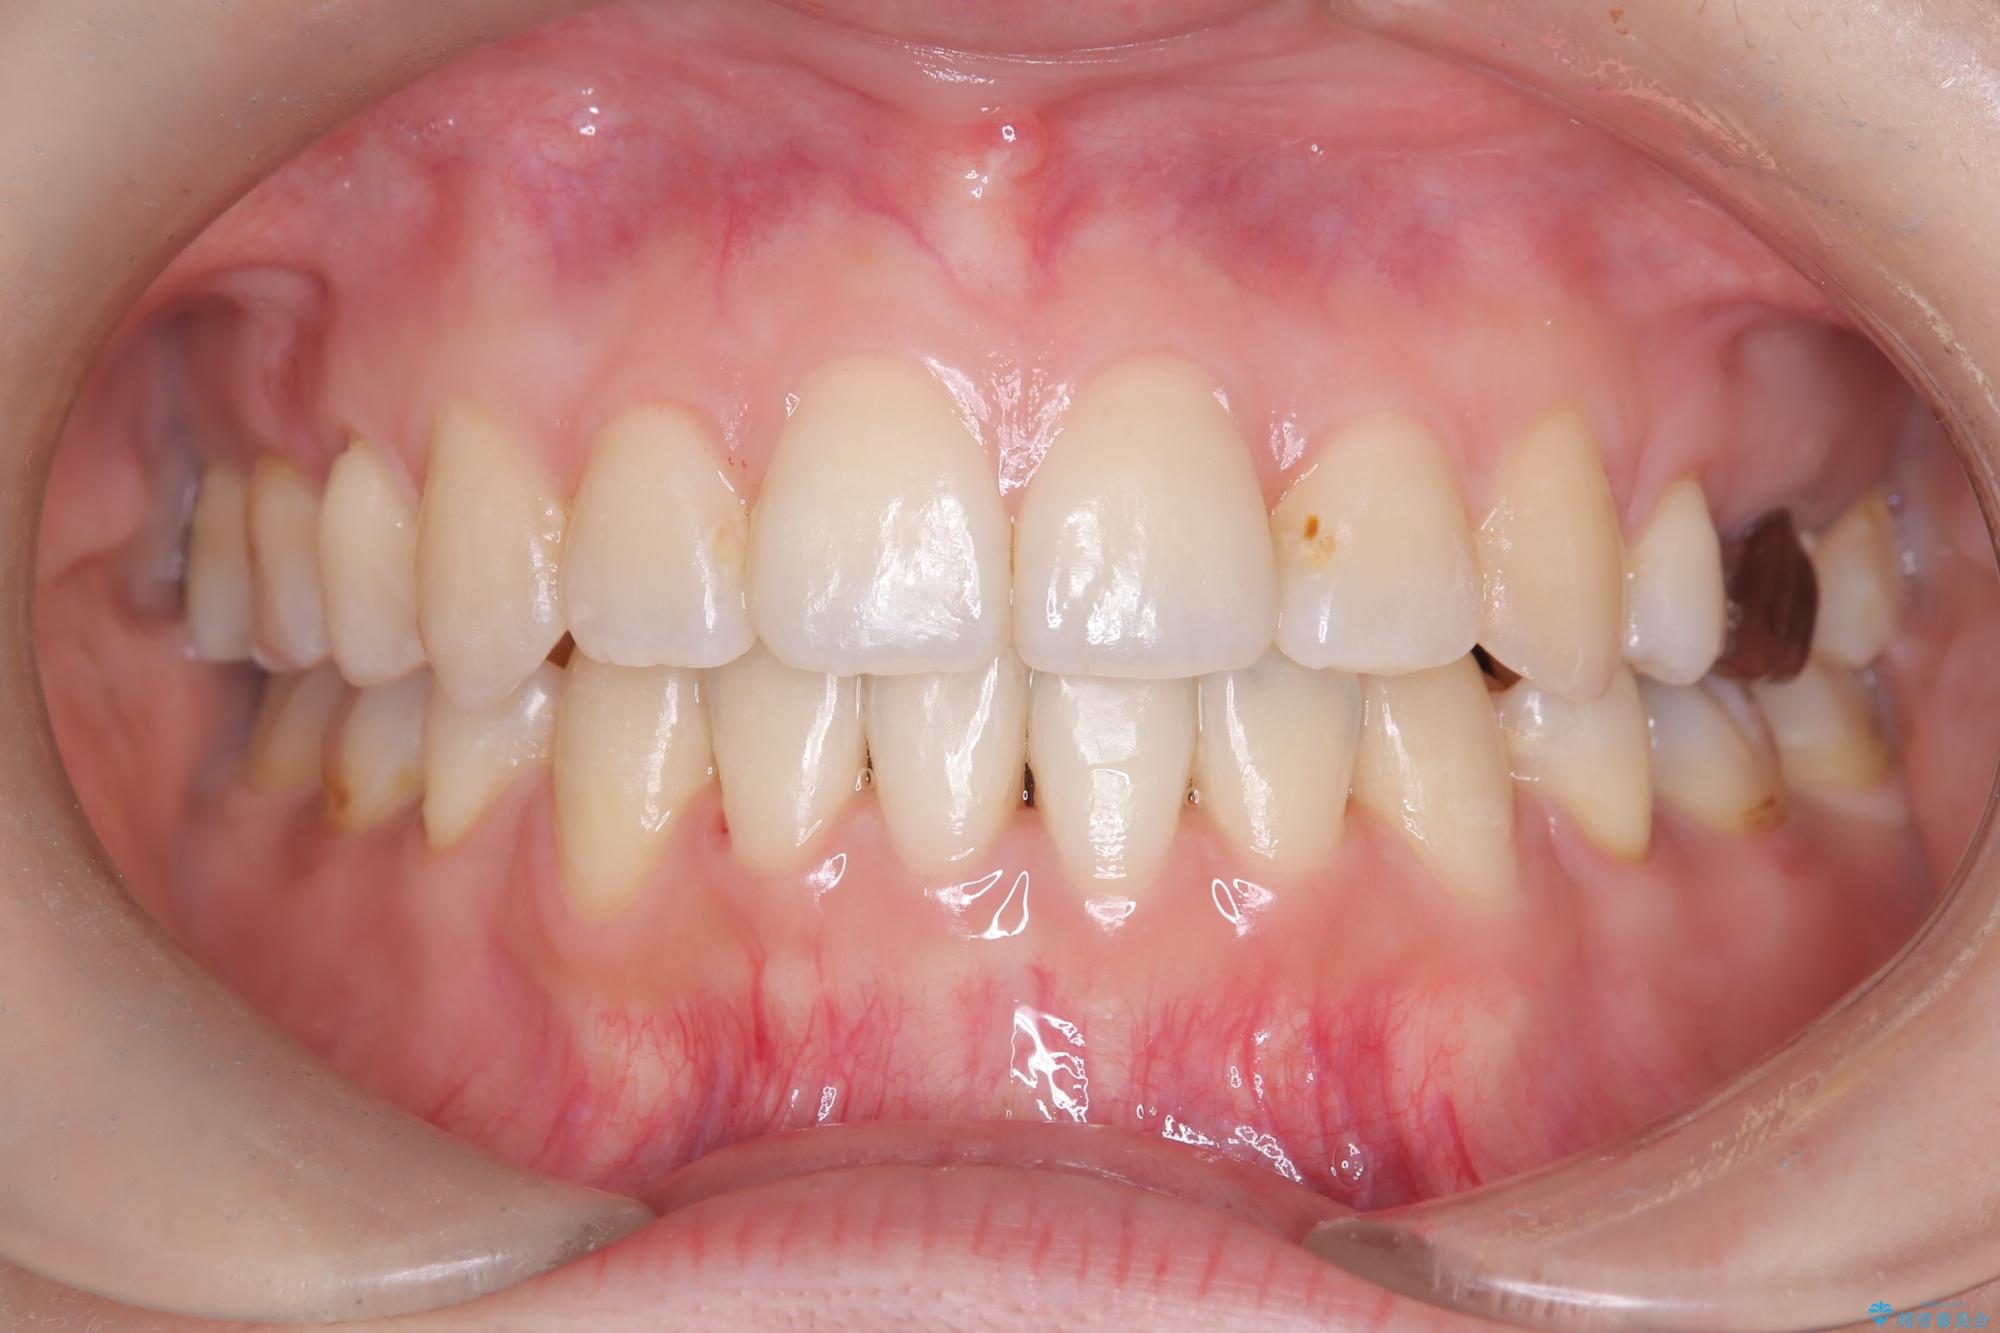

- 主訴:口元を下げて前突感を無くしたい、下の歯の凹凸も無くしたい

右側第二小臼歯、左側第一小臼歯、下顎両側第一大臼歯を抜歯しワイヤ-矯正を行いました。

骨格的顎の変位を認めたため、顔貌に対しピッタリ上下の歯の正中を合わせることは難しいと説明し、上下左右計4本小臼歯を抜歯しワイヤー矯正治療を行いました。